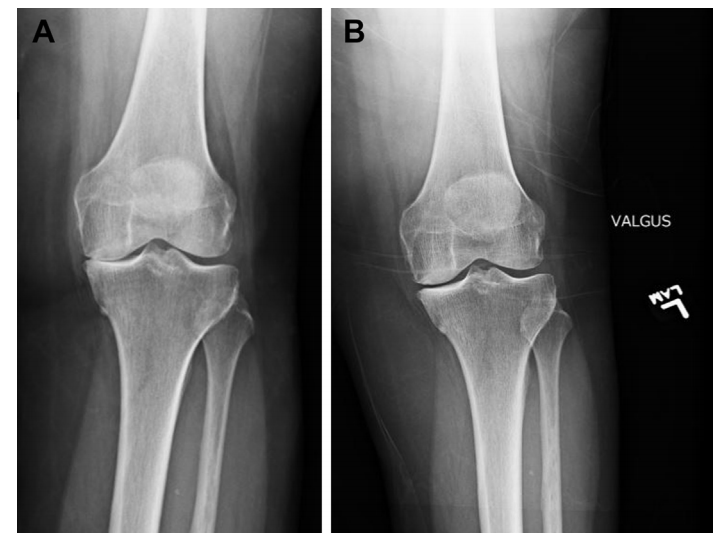

固定轴承(FB)(图3)和移动轴承(MB)(图4)是UKA的两个主要设计概念。尽管MB假体相对于FB设计的理论优势使其越来越受欢迎,聚乙烯制造的改进显著降低了FB设计中的磨损,由于聚乙烯磨损不再是FB设计的主要问题,因此UKA的设计选择仍然存在争议。

图3:固定轴承内侧UKA的X光片。

图4:可移动的内侧UKA的X光片